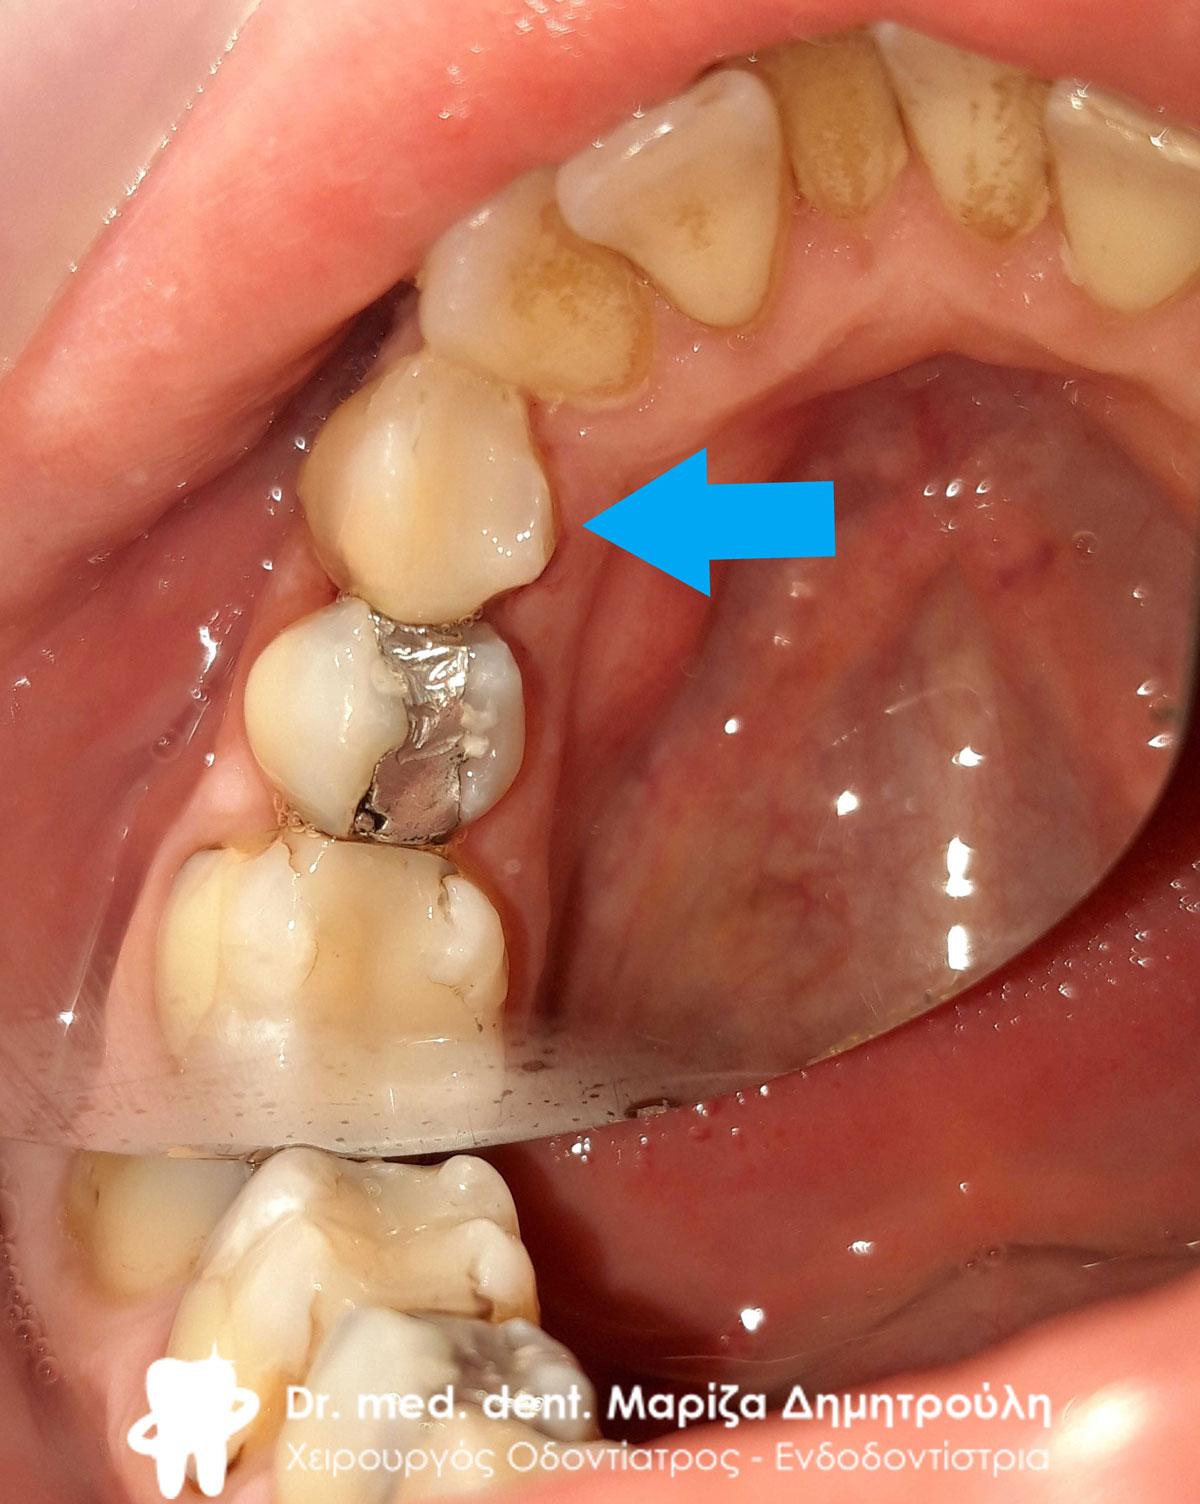

Αρχική κλινική εικόνα της αριστερής πλευράς της κάτω γνάθου

Αρχική κλινική εικόνα της αριστερής πλευράς της κάτω γνάθου

Αρχική κλινική εικόνα της αριστερής πλευράς της κάτω γνάθου

Η κυρία προσήλθε στο ιατρείο με οίδημα στην αριστερή πλευρά της κάτω γνάθου. Μετά την κλινική και ακτινογραφική εξέταση των δοντιών αφαιρέθηκε η παλιά γέφυρα που είχαν τα δόντια της. Όπως δείχνουν οι φωτογραφίες αφαιρέθηκαν με πολύ προσοχή οι παλιοί μεταλλικοί άξονες από το εσωτερικό των ριζών χωρίς να προκληθεί καμία βλάβη στα υπολείμματα των ριζών των δοντιών. Οι εναπομείναντες ρίζες δοντιών χρησιμοποιήθηκαν ως “φυσικά εμφυτεύματα” και πιο συγκεκριμένα πάνω στις ρίζες των δοντιών χτίστηκε ολόκληρο κολόβωμα δοντιού χρησιμοποιώντας ειδικούς άξονες υαλονημάτων. Στο γομφίο αφού αφαιρέθηκε η παλιά θήκη και απομακρύνθηκε ο μεταλλικός άξονας με τον ίδιο προσεχτικό τρόπο διαπιστώθηκε οτι η μία ρίζα του δοντιού ήταν πολύ κατεστραμμένη οπότε και αφαιρέθηκε. Η άλλη μισή ρίζα ανασυστάθηκε με άξονα υαλονημάτων και παρασκευάστηκε αναλόγως ώστε να δεχθεί τη μελλοντική γέφυρα ζιρκονίου. Ο πρώτος προγόμφιος επίσης προετοιμάστηκε αναλόγως (απονεύρωση και ανασύσταση δοντιού) ώστε να χρησιμοποιηθεί ως στήριγμα γέφυρας. όταν ολοκληρώθηκαν όλες οι απαραίτητες προεργασίες λήφθηκε αποτύπωμα το οποίο εστάλει στον οδοντοτεχνίτη για την κατασκευή ολοκεραμικής γέφυρας ζιρκονίου. όταν η γέφυρα ήταν έτοιμη συγκολλήθηκε στο στόμα της ασθενούς.

Αρχική κλινική εικόνα της αριστερής πλευράς της κάτω γνάθου

Αρχική κλινική εικόνα της αριστερής πλευράς της κάτω γνάθου